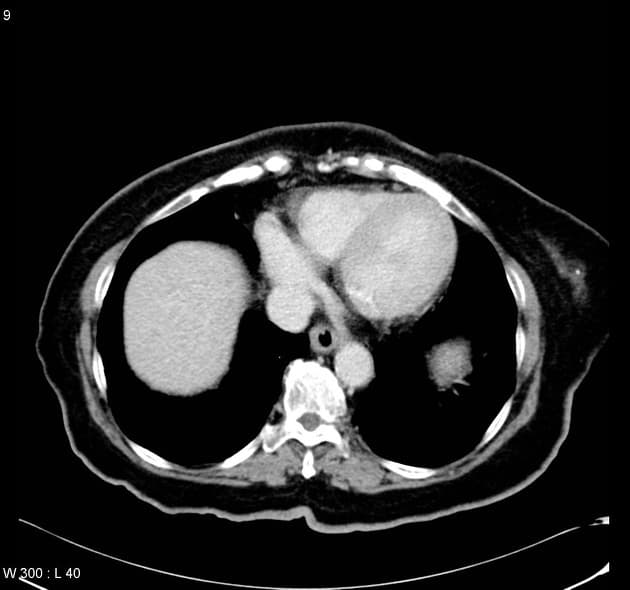

U nang ống mật chủ type III (Choledochocoele)

U nang ống mật chủ type III (Choledochocoele) trên hình ảnh chụp đường mật trong mổ và CT.

- Làm mờ hệ thống đường mật kèm giãn ống mật chủ ngoài gan.

- Giãn ống mật chủ ngoài gan trong thành tá tràng, trong lòng có sỏi.

- "Choledochocoele là dạng hiếm của u nang ống mật chủ type III, đặc trưng bởi giãn dạng nang đoạn ống mật chủ trong thành tá tràng."